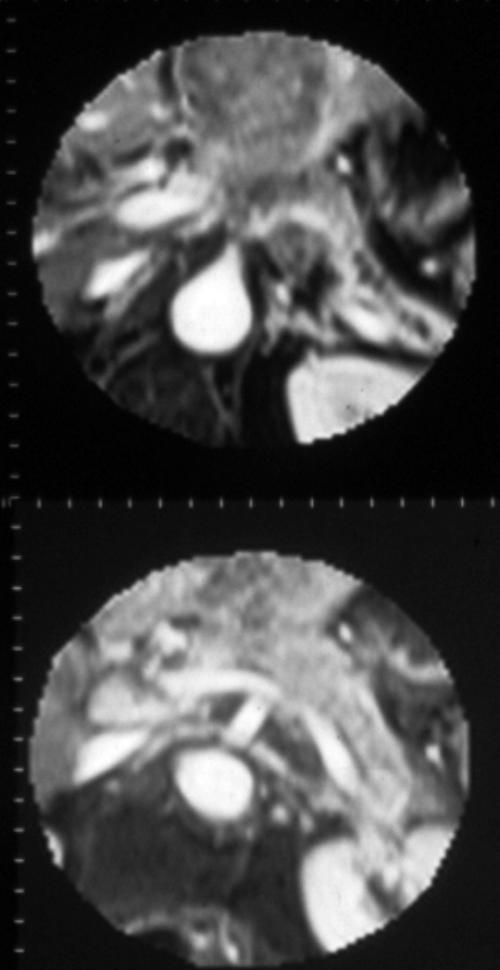

Accurate preoperative imaging evaluation of the degree of local tumor extension and peripancreatic vascular involvement are among the most important factors for predicting the likelihood of success from surgical resection and the prognosis in patients with a malignant pancreatic neoplasm. The accepted criteria for surgical resectability include [9]: tumors (<2 cm) with intact margins and without vascular involvement or metastasis. In this context, despite the fact that CT and MR show a high positive predictive value (88%), they both have a low negative predictive value (23%) [10]: in other words, if CT and MR easily determine unresectability, a large number of neoplasms judged potentially resectable on the basis of imaging findings prove not to be surgically resectable in the operating room. The limits of imaging can be summarized as follows: 1) poor sensibility to detect small metastases in the liver (<2 cm); 2) poor detection of metastasis localized on the hepatic surface; 3) poor detection of peritoneal implants and 4) low sensibility in the detection of vascular involvement particularly when neoplasms are fixed or partially encircle adjacent vessels. Since laparoscopy is the gold standard for detecting small metastases and peritoneal implants, the goal of imaging techniques is to improve the accuracy of vascular involvement. By using a biphasic dynamic MR technique, optimal peripancreatic vascular enhancement can be obtained [5] (Figure 4); in this setting, angio 3D studies do not provide further information when compared to conventional imaging.

Figure 4. Contrast-enhanced RF fast T1-weighted MR images (same case) show pancreatic neoplasm infiltrating the hepatic and splenic arteries at the origin (upper) and the splenic vein (lower). Slight dilatation of the main pancreatic duct is also visible (upper).